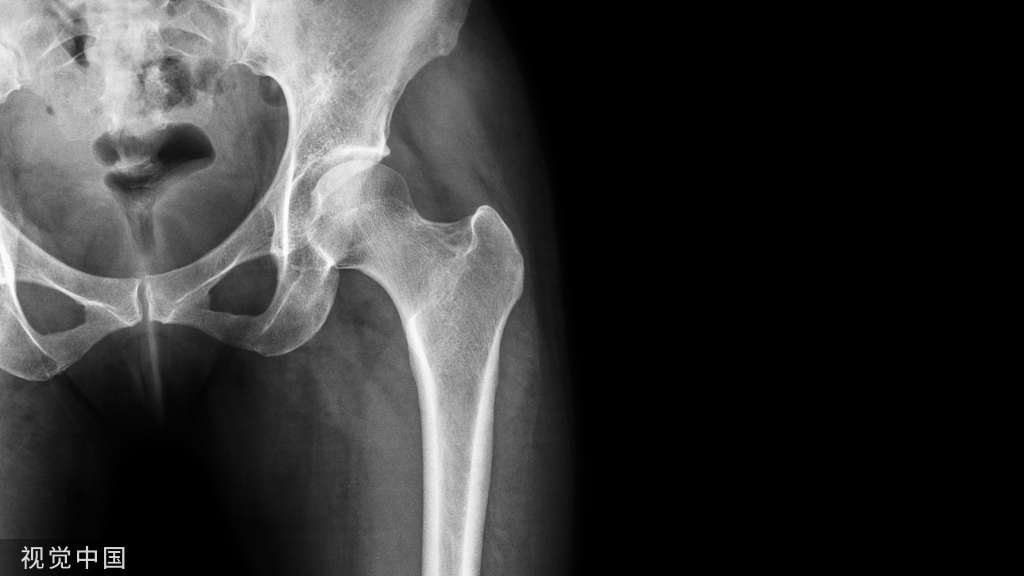

病例一患者,男,60岁主诉:摔伤致左膝部肿痛,活动受限查体:左膝部肿胀,压痛,活动受限明显。下肢血运感觉正常,各趾可自主活动。辅助检查:X片示左髌骨骨折,骨折端分离

诊断:左髌骨骨折(横行骨折)